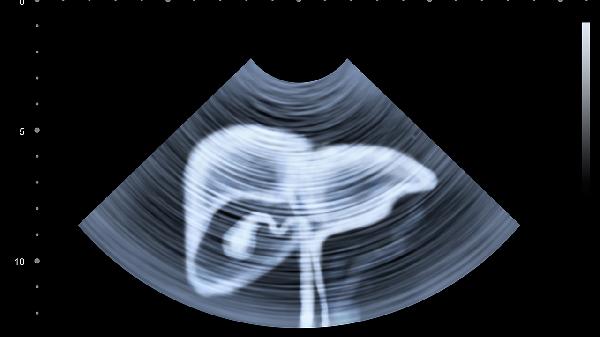

肝掌、蜘蛛痣是肝脏疾病的典型皮肤表现,与雌激素代谢异常有关。肝硬化患者常见此类症状,可能伴随毛细血管扩张。需完善肝脏超声和弹性检测,严格戒酒并避免使用肝毒性药物。